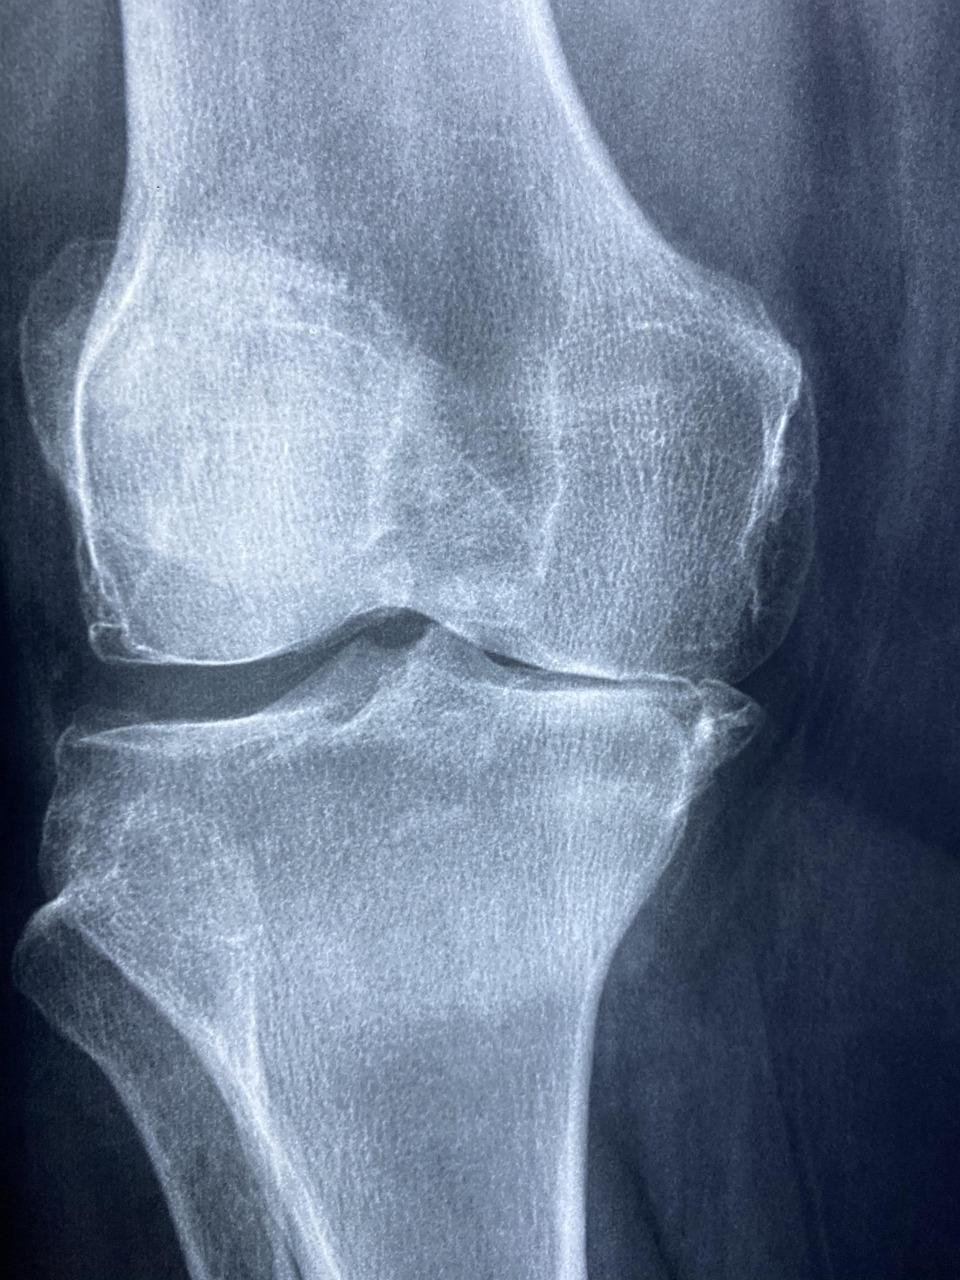

– Diagnostik mit bildgebenden Verfahren (z. B. Röntgen, MRT, Ultraschall)

Bildquelle: Bild von Dr. Manuel González Reyes auf Pixabay